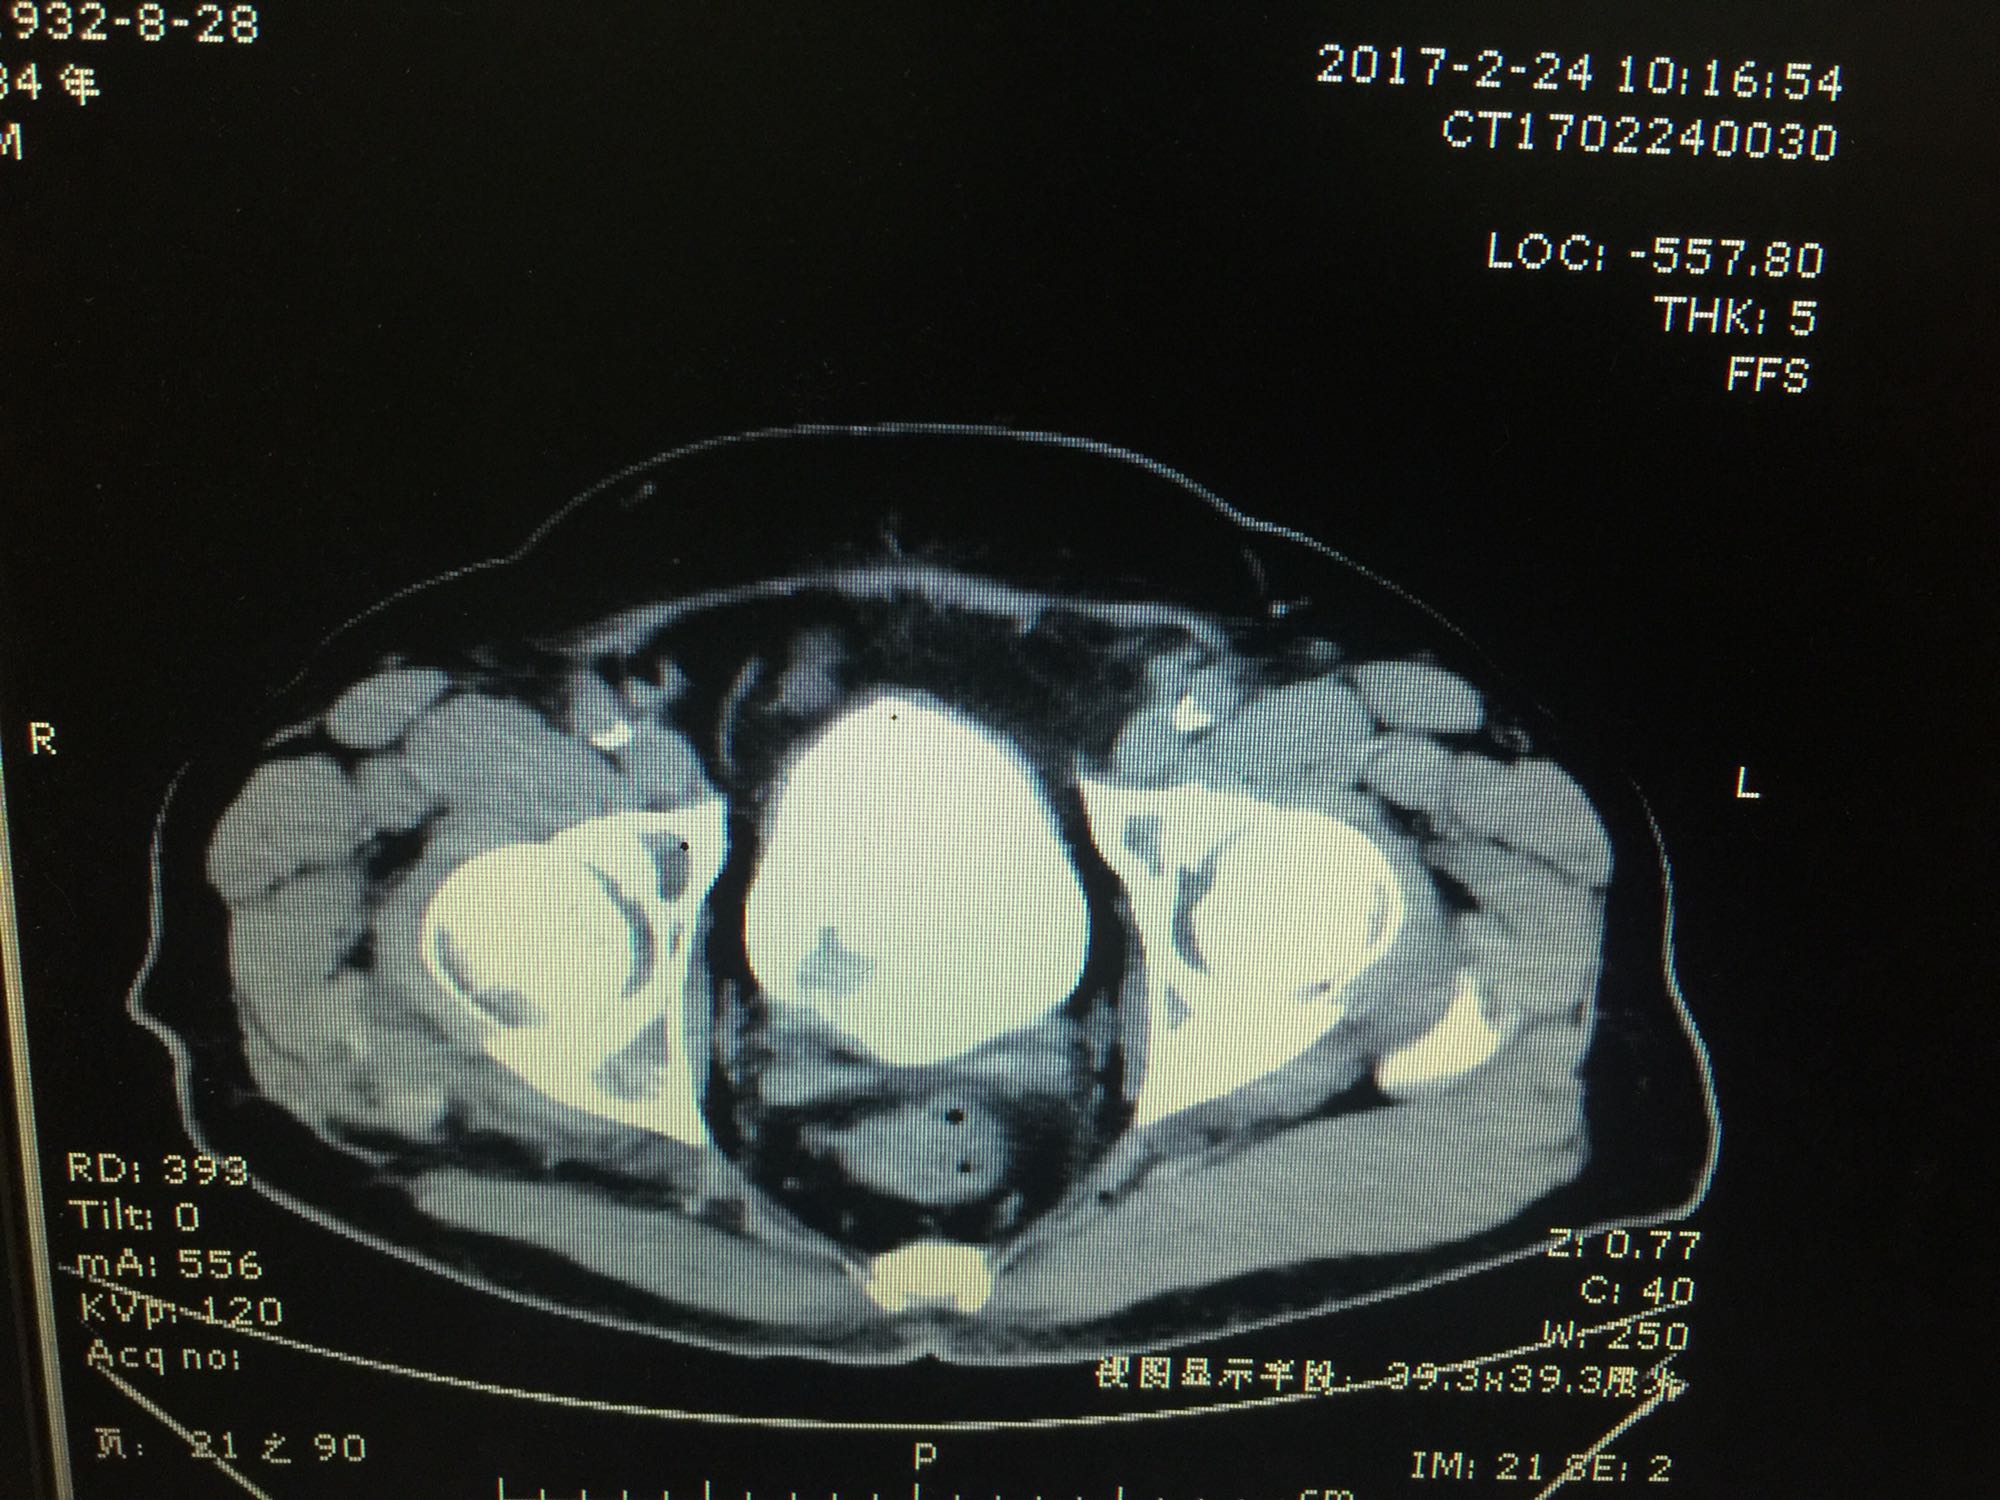

膀胱占位一例

膀胱癌

80岁男性 既往冠心病 血尿3月,发现膀胱新生物2天入院

查体:膀胱无充盈,阴囊无异常,睾丸附睾无肿大。前列腺二度大,质地中等,无压痛等